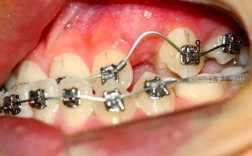

| 陶瓷托槽矫正 | 托槽采用透明陶瓷材质,接近牙齿颜色 | 半隐形效果,比传统金属托槽更美观,强度高,不易染色 |

| 舌侧矫正 | 托槽粘贴在牙齿舌侧面,完全隐藏在口腔内 | 完全隐形,社交零影响,适合对美观有极致需求的群体(如演员、主持人) |